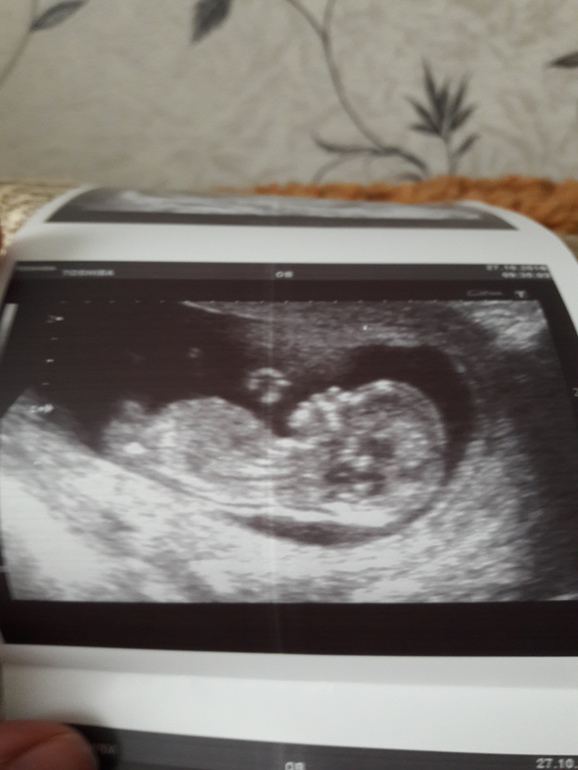

Наши будни, наши неделькиСегодня прошли первый скрининг. Папа познакомился с малышом. Все у нас хорошо тьфу тьфу, по размерам 12+5. Теперь ждем результатов крови.Я думаю, точнее уверена что все будет хорошо☺ Врач предположила что в домике живет мальчик, но сказала что писюн может оказаться и клитором, так что подождем. У кого то были похожие ситуации ( сначала мальчик а потом оказалась девочка)? Вот теперь думаю стоит ли идти на бесплатный скрининг в жк? Этот проходили платно на Опарино, я им доверяю.